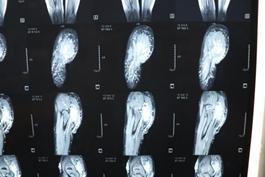

经过检查发现小诺右侧臀部及大腿有大面积的淋巴畸形,右小腿、右足踝部及右足底也有许多弥散性的肿块,不仅病变部位多且侵犯严重,加上之前已经做过三次手术,这次的手术针对医生而言无疑是巨大的挑战!经过前期充分的准备,小诺的手术如期进行,从上午10点50一直到晚上11点,历时整整12个小时,终于顺利完成手术,术中发现病变累及大面积的正常肌肉和多处神经,乔主任巧妙的采用切除和微创相结合的方式治疗病变部位,仔细分离重要的血管和神经,将大面积的病变全都切除。术后小诺身体恢复情况很好,目前正在一步步的康复,迎接她的是健康和快乐的明天!